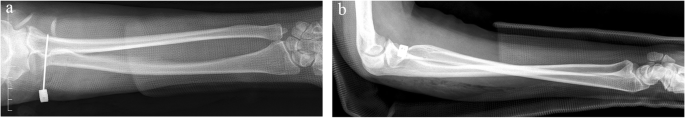

The long arm cast was kept for 4 weeks and replaced by an adjustable brace to allow a full range of flexion and extension. The K-wire was removed at 6 weeks postoperatively to allow a full range of forearm rotation. At 6 months postoperatively, the patient had regained a full range of flexion and extension, with normal supination and a slight limitation in pronation. Until 18 months postoperatively, the patient still had a slight limitation in pronation, with the Mayo elbow score being 85 and the Mayo wrist score being 90(Fig. 6). Radiographic findings revealed that the radial head and the DRUJ were in better positions, but there was still a criss-cross appearance between radius and ulna on the lateral view (Fig. 7).

After the examination, the surgery was performed, aiming to explore the lateral side of the elbow and repair the potentially injured annular ligament. A lateral approach of the elbow was performed. After dividing the subcutaneous tissues, the lateral collateral ligament revealed itself to be intact. Then, a longitudinal incision was made on the lateral collateral ligament to expose the annular ligament and the humeroradial joint. Surprisingly, the annular ligament was found to be perfectly intact, while the radial head was in a slightly anteriorly dislocated position. Further inspection of the radial head revealed an abnormal, convex and bumpy articular surface (Fig. 4). An intraoperative Valgus Elbow Stress Test showed that the radial head would dislocate anteriorly under a valgus force. To reduce the radial head, rotation of the forearm was tried first and the results were not satisfying. So we apply a manual force upon the anterior part of the radial head to achieve a well-aligned reduction while the forearm was in full supination and the elbow was in 90° flexion. Subsequently, a 2.0-mm percutaneous K-wire was used to stabilize the proximal radio-ulnar joint (PRUJ). Intraoperative radiographs showed that the radial head and the DRUJ were simultaneously reduced (Fig. 5). After closing the wound, a long arm cast was used to keep the forearm in supination, 90° of elbow flexion, and the wrist in neutral deviation.